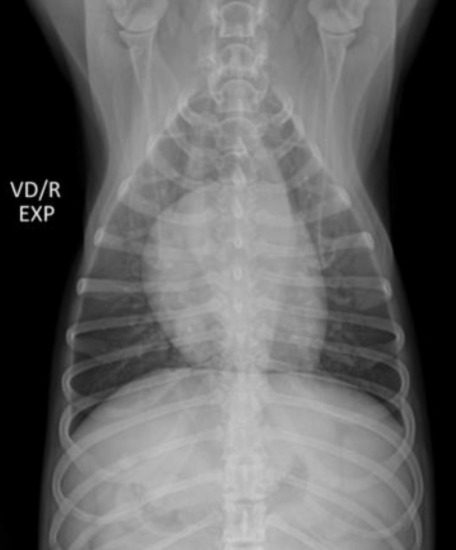

| Inspiration | Expiration |

|---|---|

![]() | ![]() |

| - ํ ๋ถ๋ถ์ด ๋ opaque (๋ฟ์๊ฒ ๋ณด์) | |

| - ํก๊ฒฉ๋ง์ด ๋ ์๋ก ์ฌ๋ผ์ ์ฌ์ฅ๊ณผ ๋ถ์ด ์์. |